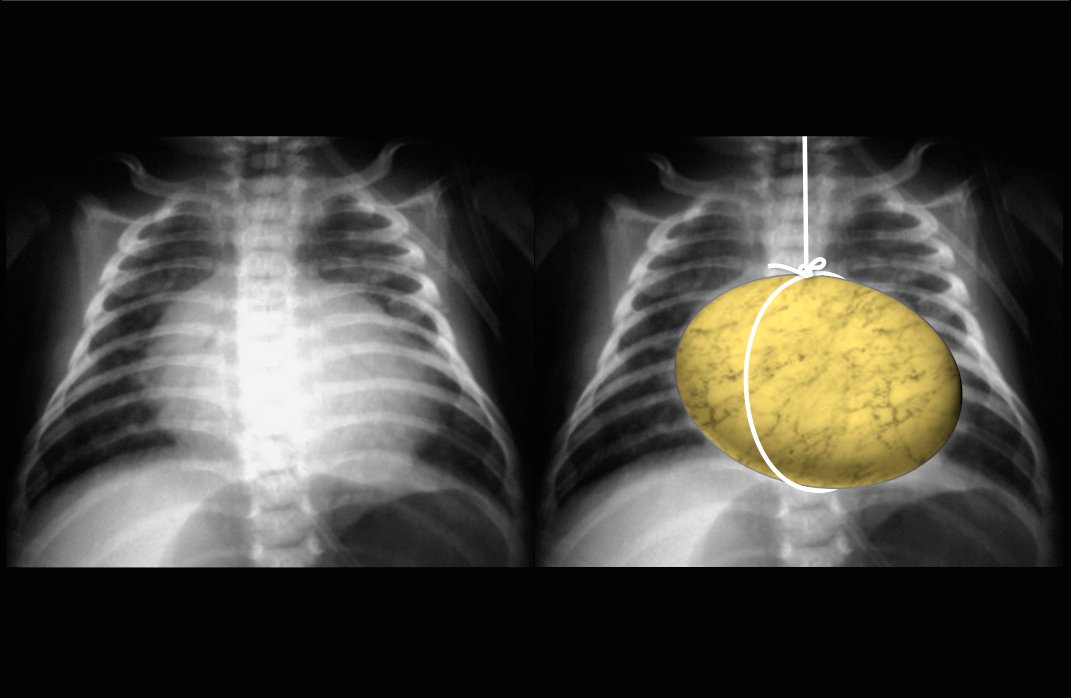

Thymus

• Spinnaker sail sign

• Indicator of pneumomediastinum

• Basically looks like ill defined opacity with lucent area underneath it and represents the thymus superiorly displaced by air in the mediastinum

• Image on left

D-TGA

• Egg on a string on CXR